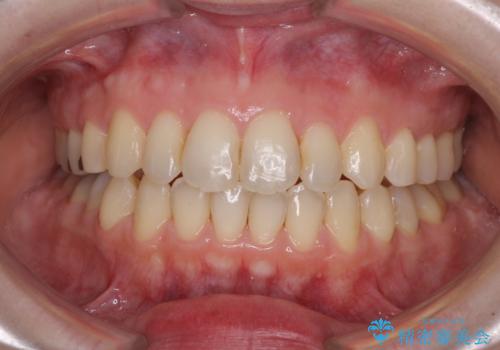

【モニター】飛び出した上顎前歯を抜歯矯正で引っ込める ワイヤー装置の抜歯矯正治療

- 口元の閉じにくさを気にして来院された患者様です。

上下ともに歯列が前方に突出していたため、上下左右の第一小臼歯4本を抜去し、ワイヤー装置による矯正治療を行うこととしました。

舌の突出癖がなかなか改善されず、上下前歯の接触がやや甘い状態での仕上がりとなりました。

接触が甘い場合、上顎前歯の叢生が後戻りを起こしやすくなるため、治療終了後の保定期間でも舌のトレーニングを継続するように指示しています。